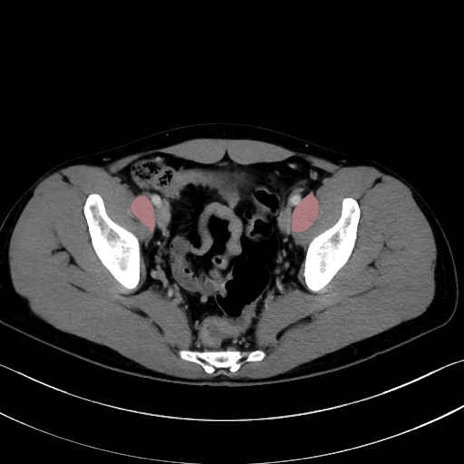

内閉鎖筋 (Obturator internus)

外閉鎖筋 (Obturator externus)